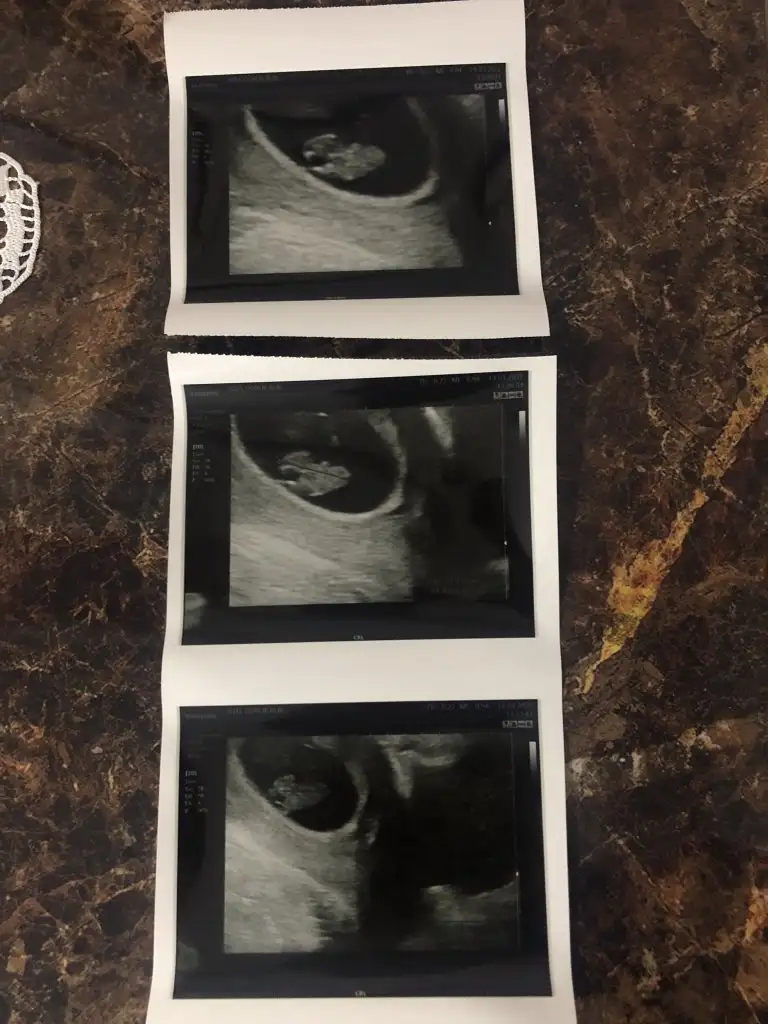

kuzuuuu iki tosun paşa bunlarŞimdi ikisinin ayrı görüntülerini de atıyorum bi de böyle bakVajinal usg

kuzum görüntüyü düz çekip atar mısın, bebek sol alttaki mi? o sanki yolk sac gibiSelam 6+3 teki foto ile ben de geldim

Çok merak ediyorum lütfen cevaplar mısın9+5 zamanından ultrason görüntüsü. Karından bakıldı, bana da bakar mısınız rica etsem çok merak ediyorum :)

kuzum karından bakılmıştır diye tahmin ediyorum. Tosun paşa gibi duruyor.Merhaba. Ultrason fotoğrafım tam 8 haftalıkken. Bana da tahminde bulunabilir misiniz acaba. Çok teşekkür ederim.